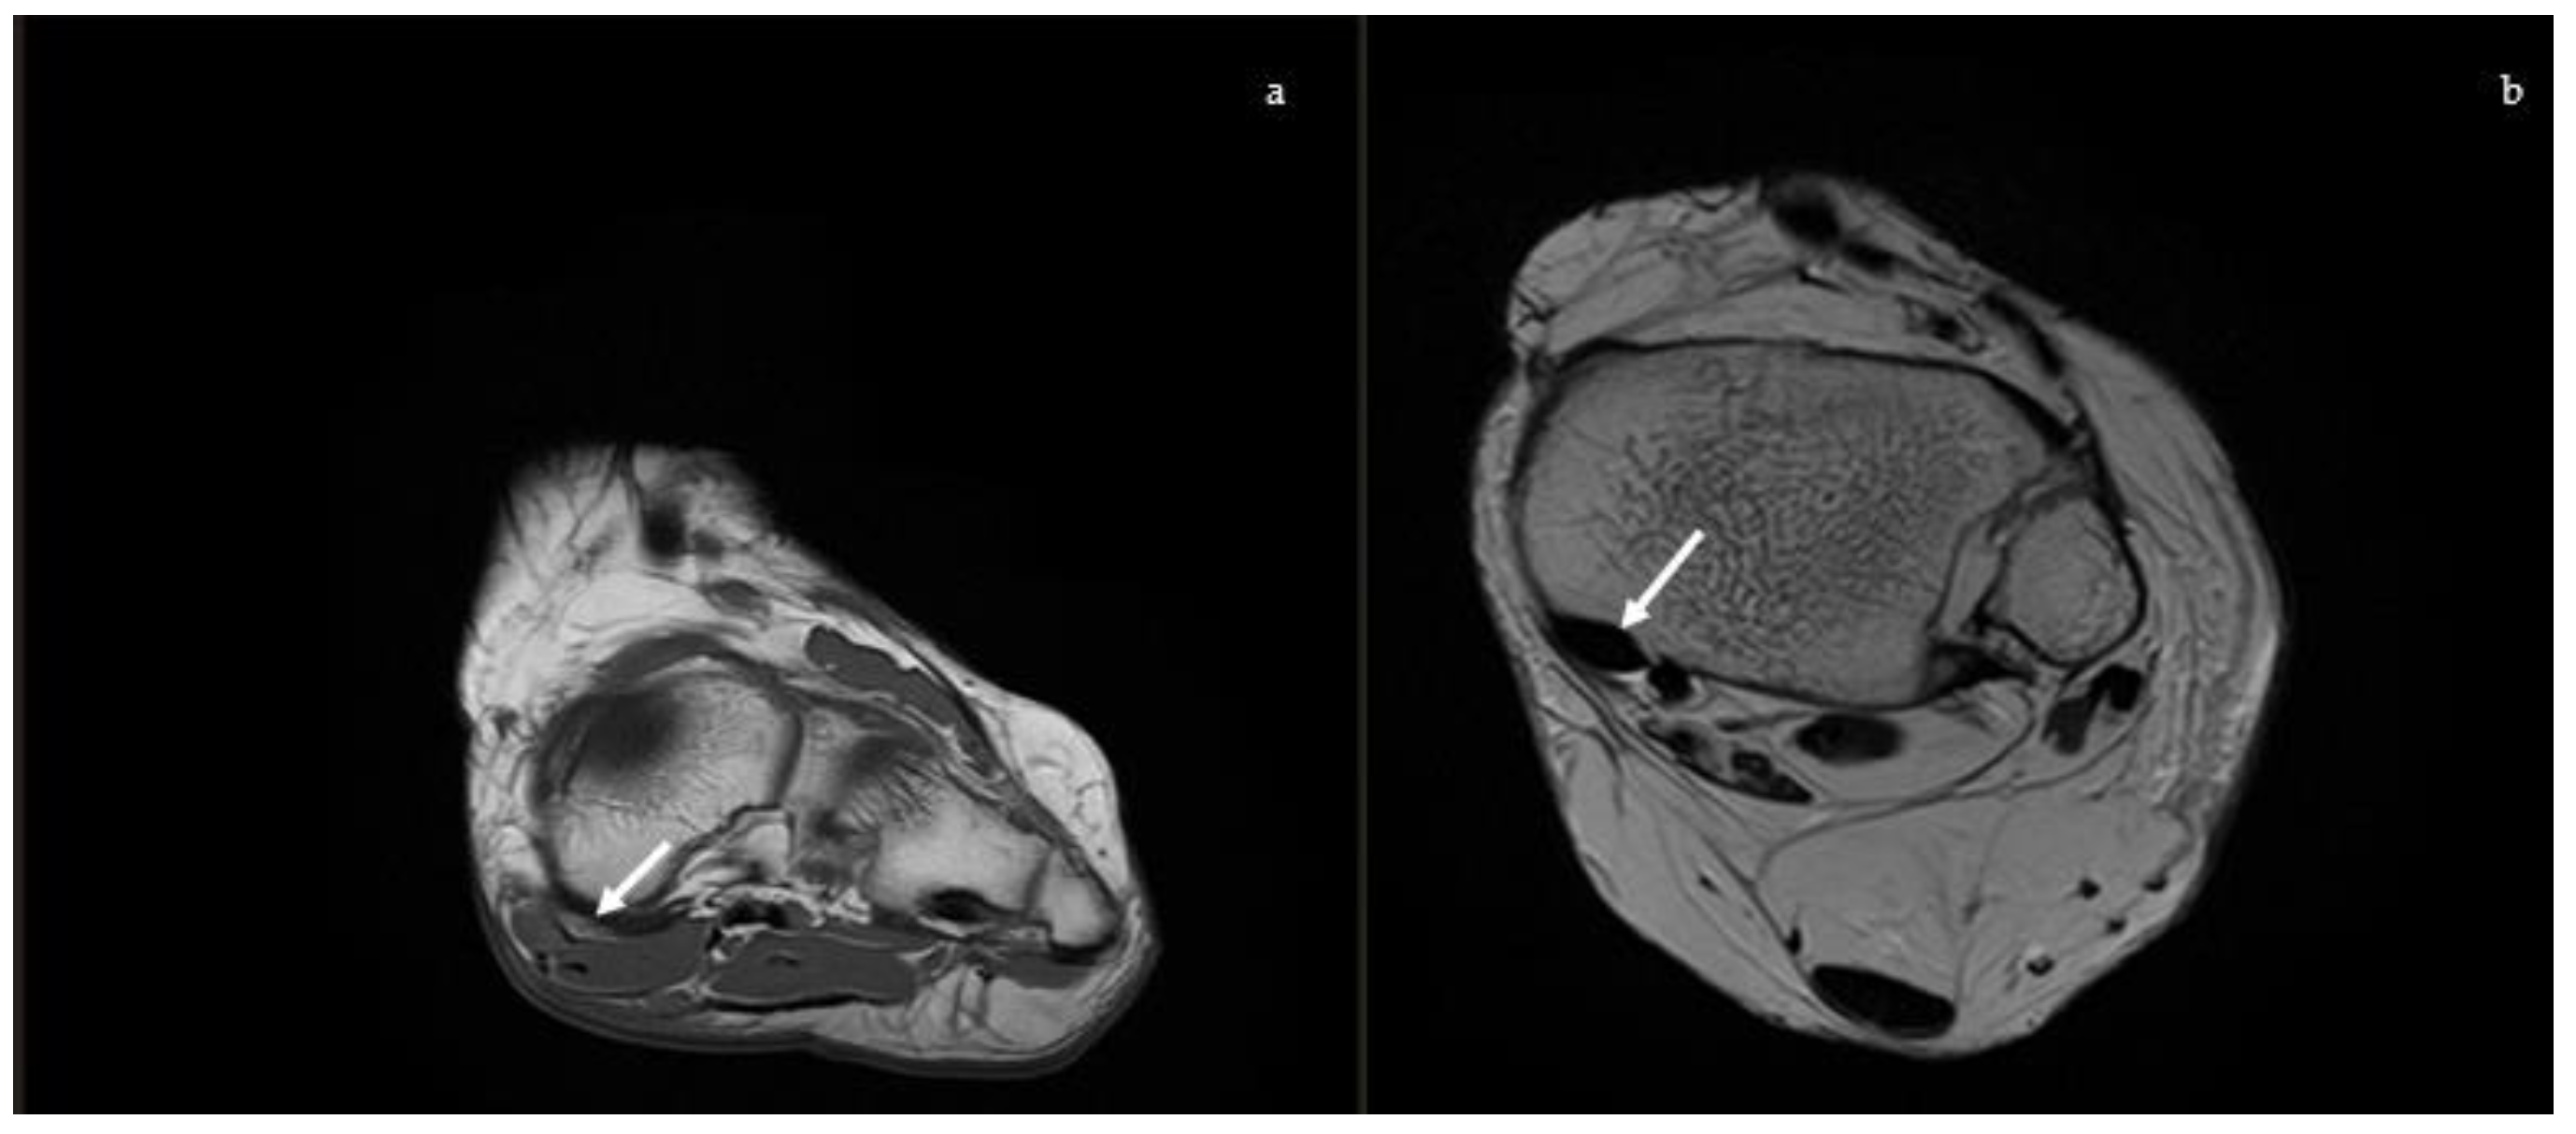

2.2.1. Posterior Tibial Tendon

2.2.2. Spring Ligament